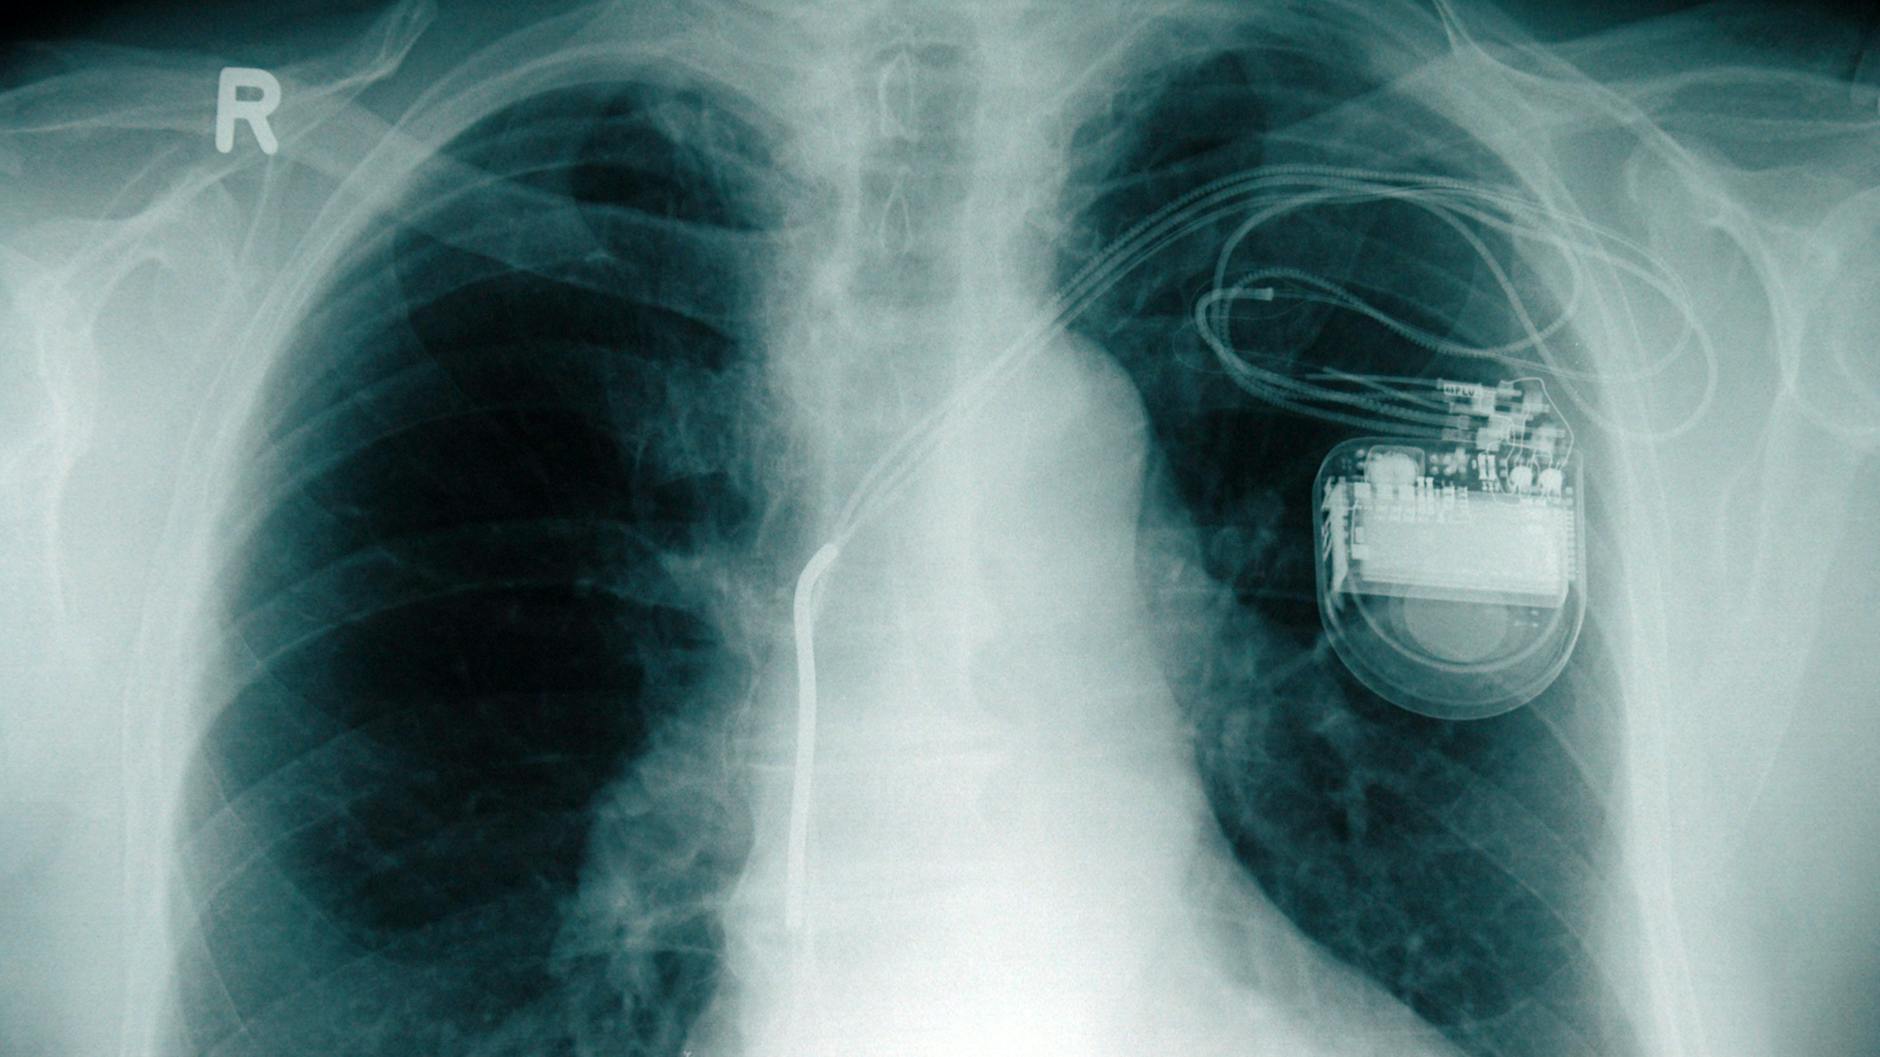

Magnetfelder mit einer bestimmten Stärke können Herzschrittmacher und Defibrillatoren stören. Daher rät etwa Apple seinen Kunden, mit verschiedenen Geräten mindestens 15 Zentimeter Sicherheitsabstand zu solchen Implantaten zu halten – darunter die iPhones 12 und 13. Apple listet außerdem unter anderem auch Tablets, Laptops, Smartwatches und kabellose Ohrstöpsel auf.

Was haben Lacour, Blaschke und ihre Kollegen herausgefunden? Kurz: Die iPhones 12 und 13 mit ihren Ringmagneten (MagSafe-Technologie) können die Funktion von Schrittmachern und Defibrillatoren beeinflussen. Aber nur bei ganz nahem Kontakt, und auch nicht bei allen Implantaten, wie die Untersuchung zeigte.

Das ist auch, was Philipp Lacour und Florian Blaschke sagen. In ihrer im November 2021 veröffentlichten Studie haben sie alle auf dem Markt verfügbaren kardialen Implantate mit der Magnetfeldstärke, die diese iPhones konstant ausstrahlen, getestet. Dafür wurden im Labor das iPhone 12 und die Implantate in möglichst engen Kontakt gebracht.

Das Ergebnis: Beeinflussungen gab es ungefähr bei der Hälfte der kardialen Implantate. Und auch dann nur bei ganz geringen Abständen zwischen Ringmagnet und Implantat. „In der Regel maximal ein Zentimeter“, sagt Lacour.

Oft liegen Schrittmacher oder Defibrillatoren im Körper unter den Haut- und Fettschichten aber schon mehr als einen Zentimeter tief, so der Kardiologe weiter. So überrascht es kaum, dass die Zahl der Störungen dann beim Test mit 164 Implantat-Trägern im Vergleich zum Test der Implantate außerhalb des Körpers schon deutlich abnahm.

Bei den Patienten gab es in der Untersuchung durch das Auflegen des iPhones auf die Brust nur in 18 Prozent der Fälle eine Interaktion. Und: Schon wenn das Display des Smartphones zum Patienten zeigte, kam es laut Florian Blaschke zu keiner Interaktion mit den implantierten Schrittmachern oder Defibrillatoren. Der Magnet liegt eben an der Rückseite des iPhones. Folglich ist das Magnetfeld dort stärker.